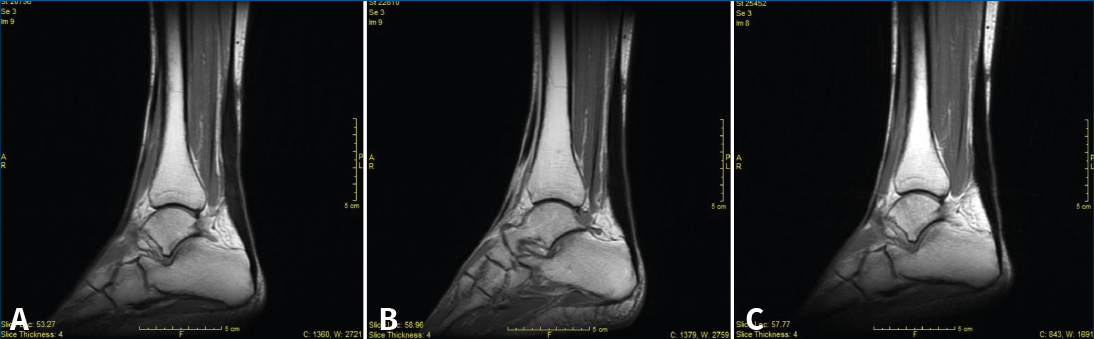

Figura 3. Secciones sagitales de resonancia magnética de SE T1, a los 3 (A), 6 (B) y 12 meses (C).

A los 3, 6 y 12 meses se recogió el balance articular del tobillo, el diámetro de la pantorrilla, la altura del talón al suelo bipodal y el grosor del tendón. Se pasaron los cuestionarios AOFAS, SF-36 y ATRS, y también se realizaron RM (Figura 3) y ecografía. A los 12 meses se practicó una exploración dinamométrica isocinética.

Los hallazgos en las RM y las ecografías de control se encuentran recogidos en las Tablas 1 y 2. En la Figura 3 podemos observar el característico engrosamiento tendinoso durante la evolución postoperatoria. Las complicaciones postoperatorias quedan recogidas en la Tabla 3.

Karjalainen et al. en 1997 publican un trabajo en el que realizan RM a 21 pacientes postoperados de roturas del tendón de Aquiles y observan que existe una correlación entre la mala evolución clínica y la existencia de lesiones intratendinosas con señal de alta intensidad(23). Igual que en el estudio de Karjalainen et al., en nuestro estudio se midió el área mayor del tendón y se comparó con el tendón contralateral, además de valorar cualitativamente las imágenes de RM(23). Los hallazgos más frecuentes mediante RM en ambos grupos de tratamiento fueron el engrosamiento, la heterogeneidad y el líquido peritendinoso. En 4 pacientes se encontró hiperseñal intratendinosa, que según Karjalainen et al. (1996) podría corresponder a formación de cicatriz fibrosa en el interior. Ellos encontraron este tipo de lesión en 4 de los 13 pacientes estudiados y, de ellos, los 2 con las lesiones más grandes fueron los que tuvieron una peor evolución clínica(24). En nuestro estudio, sin embargo, los 4 pacientes presentaban una correcta evolución.

Globalmente, en nuestro trabajo, los resultados tanto de la RM como de la ecografía mostraron cambios heterogéneos y engrosamiento en la mayoría de los pacientes como hallazgos más frecuentes. Este dato no mostró una significación clínica. En cambio, sí que pareció existir una relación entre el adelgazamiento tendinoso y la mala puntuación de los cuestionarios funcionales. Estos resultados sugieren que el adelgazamiento es un factor de riesgo o un indicador precoz de una posible rerrotura o de una mala evolución funcional.